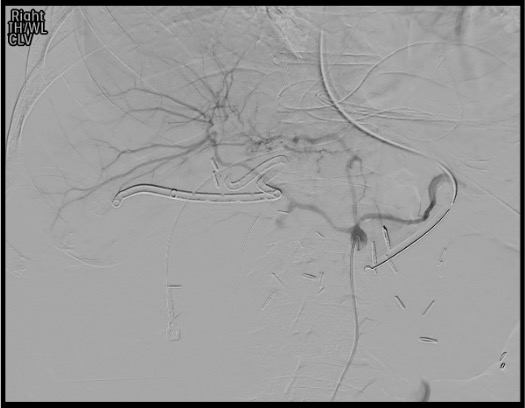

- Covered stent principle: Stent is placed in CHA spanning the GDA stump origin, maintaining hepatic perfusion while excluding the bleeding stump. Hepatic flow is preserved — liver does not lose its blood supply.

Celiac angiogram

Selective CHA angiogram and Exchange

Treatment decision: covered stent vs coil embolization

Covered stent deployment

Completion angiogram